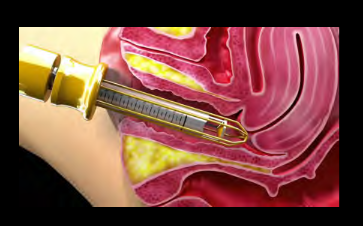

Gynecology Handpieces

CO2 fractional laser causes a controlled and highly precise photothermal effect into the vaginal mucosa, promoting tissue contraction and tightening and returning its natural elasticity to the vaginal canal. The laser energy delivered along the vaginal wall heats the tissue without damaging it and stimulating the production of new collagen in the endopelvic fascia.